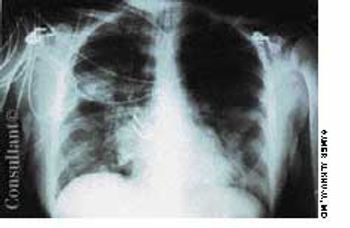

A febrile 65-year-old woman who had suffered a new-onset seizure was brought to the emergency department. The patient-a cigarette smoker-was not coughing and had neither chest pain nor a significant medical history. Her temperature was 39.4°C (103°F). She had nuchal rigidity and Kernig's and Brudzinski's signs of meningeal irritation. Lung auscultation revealed signs of right middle lung consolidation. Her white blood cell count was 1,200/µL. A chest film, seen here, showed a masslike density in the right midlung.